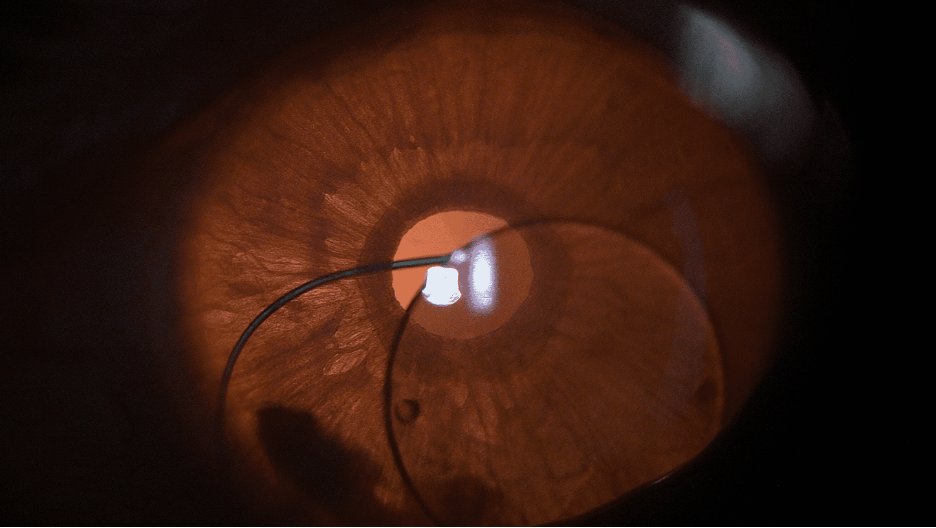

A new episode of MIGS Success Surgical Secrets is out now. Constance Okeke, MD, focuses on the STREAMLINE Surgical System.